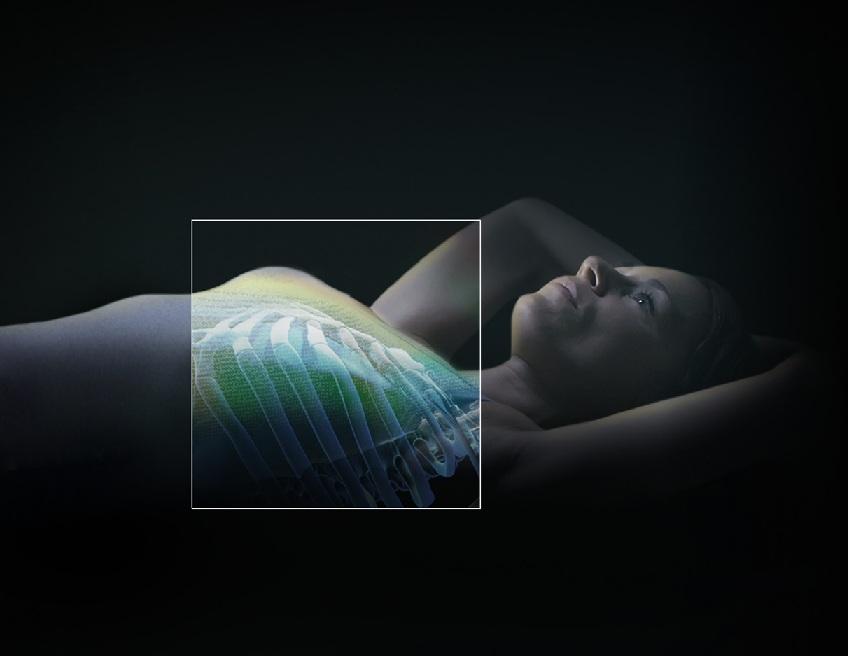

SGRT体表面誘導放射線治療システム(ExacTrac Dynamic Surface)

SGRT(Surface Guided Radiation Therapy)は、患者さんの体表面をカメラで三次元的に取得し、その形状を基準データ(治療計画CTから生成された体表面)と比較することで、患者さんの位置ずれを非接触で高精度に検出する技術です。

ExacTrac Dynamic Surface では、3Dステレオカメラ、構造化光、赤外線サーマルカメラなどを用いて体表面をリアルタイムにスキャンし、数十万点に及ぶ三次元表面データを取得します。これにより、体表面の形状と温度情報を組み合わせた高精度な位置追跡が可能となります。

さらに、X線画像による内部構造の確認を組み合わせることで、骨構造などの内部位置情報を含めた精密な位置合わせが可能です。これにより、従来の皮膚マークを使用しない治療が可能となり、特に乳房温存照射において患者さんの精神的負担の軽減に貢献します。